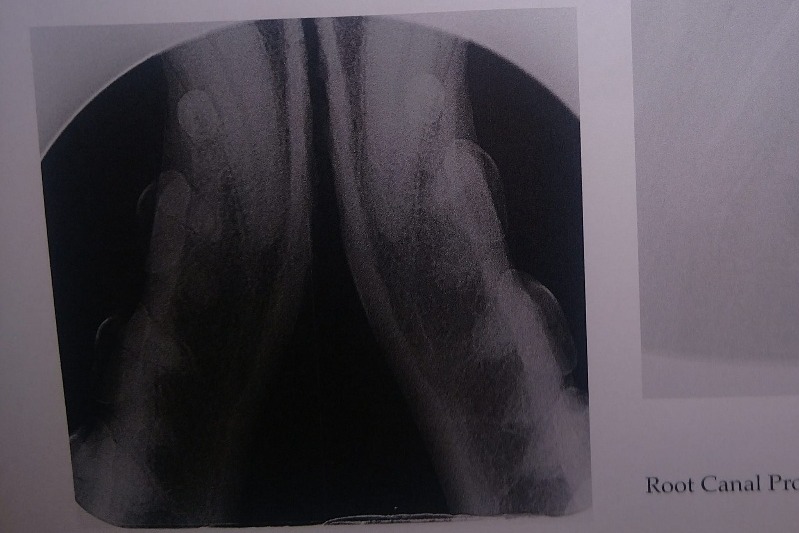

AFTER PHOTOS: (left upper and lower canine root canals, cleaning)

The following photos are her radiographs for anyone that knows how to read them, so you can see all the dead teeth that need future extractions, and some show the root canals: